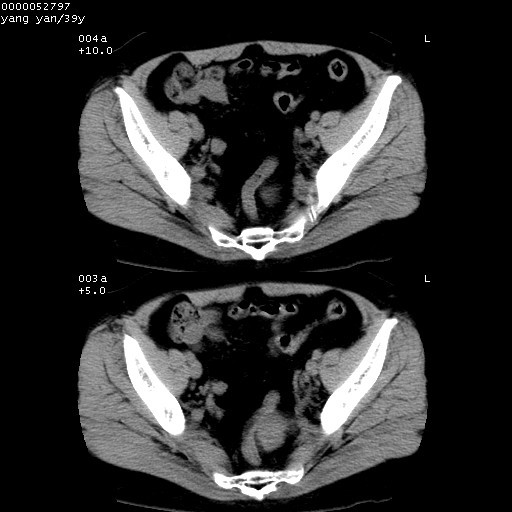

患者 女,39岁。因外伤检查,偶然发现。

典型!双侧骶髂关节致密性骨炎。

典型!病变主要累及双侧髂骨。常见于育龄期妇女。

致密性骨炎,一般不跨越关节面,可是这个骶骨关节面也有硬化。

髂骨致密性骨炎系一种以骨质硬化为特点的非特异性炎症,有高度致密的骨硬化现象,尤其以髂骨下2/3更为明显,但关节间隙则无改变。因位于骶髂关节,且该关节症状明显,故又称之为“骶髂关节致密性骨炎”。 本病90%以上为中年女性,以妊娠后期、尤其分娩后为多见,亦可见于尿路或女性附件慢性感染后,或盆腔内其他感染。此外,臀骶部的外伤亦可诱发或引起本病。  妊娠、分娩及外伤均可引起骶髂关节韧带的撕裂而易使局部的血供受阻。因此早期局部呈现充血、水肿及渗出增加等,渐而局部出现增生与变性反应,随着胶原纤维的致密化而向硬化演变;血管形成厚壁血管,易闭塞而引起髂骨耳状面处缺血和缺氧,骨质呈现硬化性改变,以致手术时局部出血较少。骶髂关节囊壁显示纤维增生、弹性降低及松动样改变。继发于盆腔内炎症者亦出现相类似的病理改变,可能系细菌内毒素作用所致。